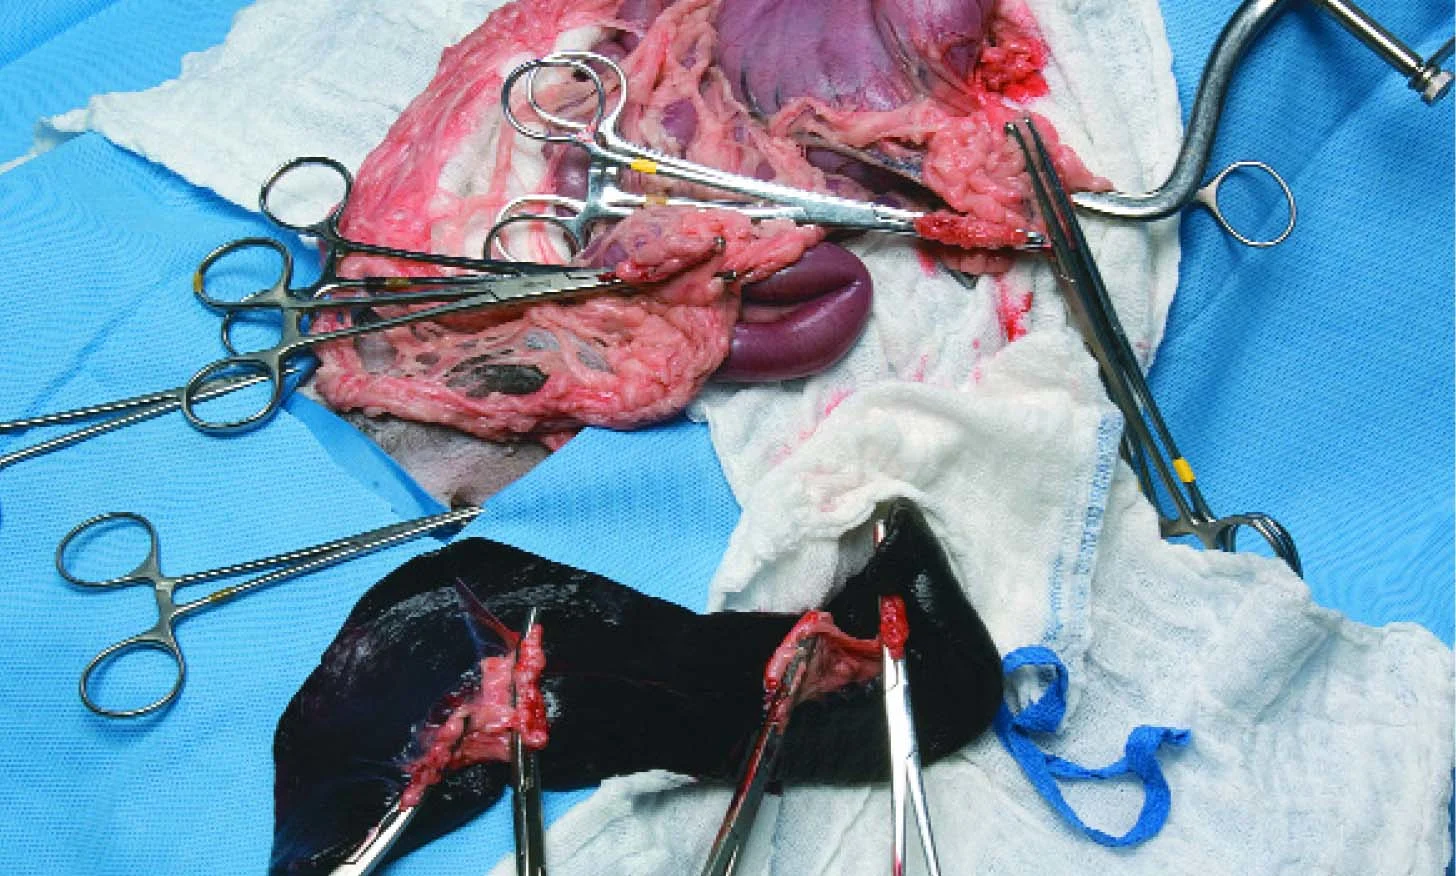

Remove the spleen with the associated forceps still attached to the pedicles and submit for biopsy. The figure shows a completed splenectomy showing 4 clamped pedicles (forceps #3) on the spleen.